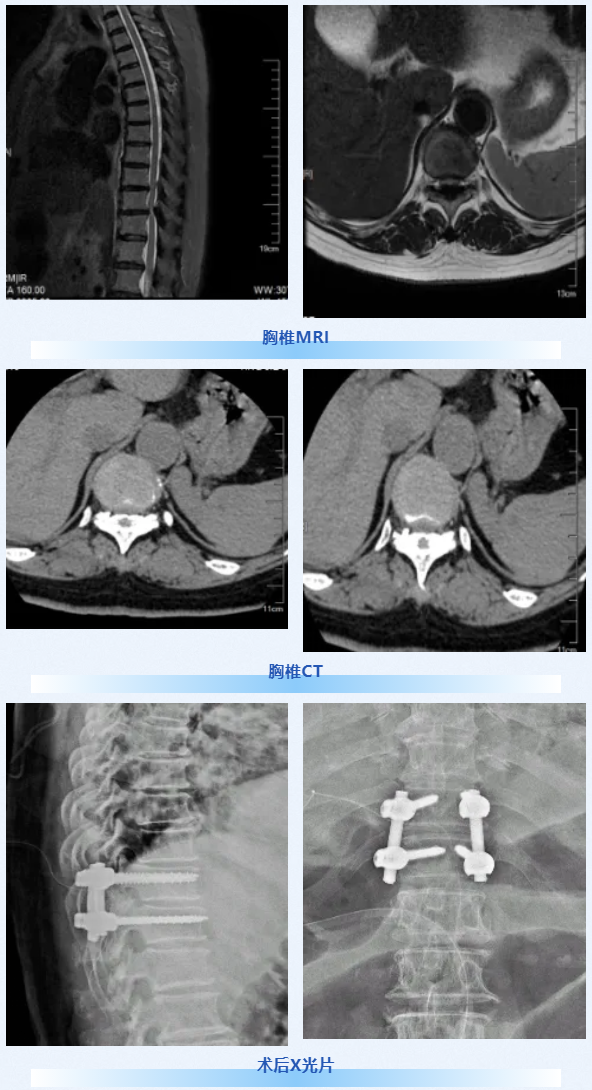

病例详情

患者为60岁女性,既往存在双下肢轻度无力、轻微麻木症状。此次因不慎摔倒后,出现腹股沟以远区域针刺样疼痛,双下肢无力加重至无法行走,活动受限,同时伴大便干燥、小便尿不净及尿急表现。

治疗及预后

患者术后双下肢针刺样疼痛即刻消失,双下肢肌力显著改善,大小便功能恢复良好。术后1周可坐起并借助助行器离床进行功能锻炼;术后1个月复查提示胸椎融合效果理想,患者已可脱离助行器独立完成离床功能练习。

术前

术后